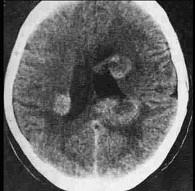

问题 男,38岁,3个月前行肺癌切除术,近3周来出现头痛、呕吐及阵发性意识错乱并有2次癫痫发作。检查:神情淡漠,视乳头鼻侧边缘模糊,胸部除前次术后一般改变外,无其他重要发现,血沉50mm/h,头颅超声波检查:中线波无偏移,脑电图:双侧弥漫性异常,头部CT扫描显示双侧大脑半球皮质及皮质下区多个小圆形低密度灶(如图所示)。处理应为()

选项 A.开颅探查切除病灶 B.行脑脊液分流术 C.应用中草药,化学治疗等相结合的非手术治疗措施 D.给予吗啡类药物以缓解症状 E.输血

答案 C